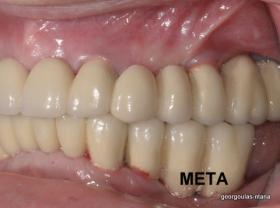

ΟΛΙΚΗ ΑΠΟΚΑΤΑΣΤΑΣΗ ΑΝΩ Κ ΚΑΤΩ ΓΝΑΘΟΥ ΜΕ ΕΜΦΥΤΕΥΜΑΤΑ, ΑΜΕΣΗ ΦΟΡΤΙΣΗ Κ ΑΝΟΙΚΤΗ ΑΝΥΨΩΣΗ ΙΓΜΟΡΕΙΟΥ

Η ασθενής αυτή είχε παλιές ακίνητες αποκαταστάσεις (γέφυρες) στην άνω γνάθο  κ μια κινητή προσθετική αποκατάσταση (μερική οδοντοστοιχία-"μασελάκι") στην κάτω γνάθο. Ήταν δυσαρεστημένη τόσο με την εμφάνιση όσο και με τη λειτουργία των δοντιών της καθώς παραπονιόταν ότι  είχαν εντονη κινητικότητα ενώ και οι προσθετικές τους εργασιές δεν ήταν σταθερές. Η πρόγνωση των δοντιών κρίθηκε φτωχή με αποτέλεσμα να μην είναι δυνατή η συμμετοχή τους σε μια νεα προσθετική αποκατάσταση με μακροχρόνια διάρκεια. Η ασθενής επιθυμούσε οι νέες αποκαταστάσεις να είναι σταθερές και ακίνητες.  Για το λόγο αυτό αποφασίστηκε η ολική αποκατάσταση της άνω κ κάτω γνάθου με ακίνητες επιεμφυτευματικές εργασίες. Στην αριστερή πλευρά της άνω γνάθου, λόγω μη επαρκούς οστού για την τοποθέτηση εμφυτευμάτων προηγήθηκε επέμβαση ανοιχτής  ανύψωσης ιγμορείου άντρου με τη χρήση πιεζοχειρουργικού μηχανήματος ώστε να δημιουργηθεί το κατάλληλο οστικό υπόστρωμα. Ακολούθησε σε επόμενο χειρουργείο η εξαγωγή των υπάρχοντων δοντιών κ η άμεση τοποθέτηση εμφυτεύματων (άμεση εμφύτευση) κ δύο μέρες μετά η τοποθέτηση προσωρινής εργασίας επί των εμφυτευμάτων (άμεση φόρτιση) με αποτέλεσμα η ασθενής να μη μείνει καθόλου χωρίς δόντια κ να είναι καλυμένη αισθητικά όσο καιρό διήρκησε η εργασία